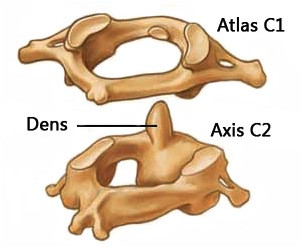

Upper cervical chiropractic is a unique field of alternative healthcare that focuses on maintaining the delicate balance between the top two bones of the neck (known as the upper cervical spine), the skull, and the nervous system. The upper cervical spine consists of the atlas (C1) and axis (C2). These two bones are completely different from all other vertebrae in shape and movement. This area of your spine is truly the power switch of the body because of its intimate relationship with the brain and brain stem.

Trauma from events such as falls, auto accidents, or a stressful birth process can cause misalignments in the upper cervical spine that throw the nervous system out of balance. This is what chiropractors call a “subluxation” – a misalignment of a vertebra that puts pressure on a nerve. However, when C1 or C2 are subluxated, it’s not just any nerve that gets affected! A upper cervical subluxation can cause irratation to the brain stem and spinal cord thus affecting the health of the body globally.

Upper Cervical doctors concentrate primarily on the top two vertebrae of the neck (called C1 and C2) to affect the rest of the spine and body as a whole. When these vertebrae are out of alignment, it unbalances the head causing the whole spine and body to compensate.

The top two vertebrae of the neck have a very intimate relationship with the brain and nervous system that the rest of the spine does not. Problems with these vertebrae can result in dysfunction of the brain particularly the brain stem, which controls millions of functions in the body.